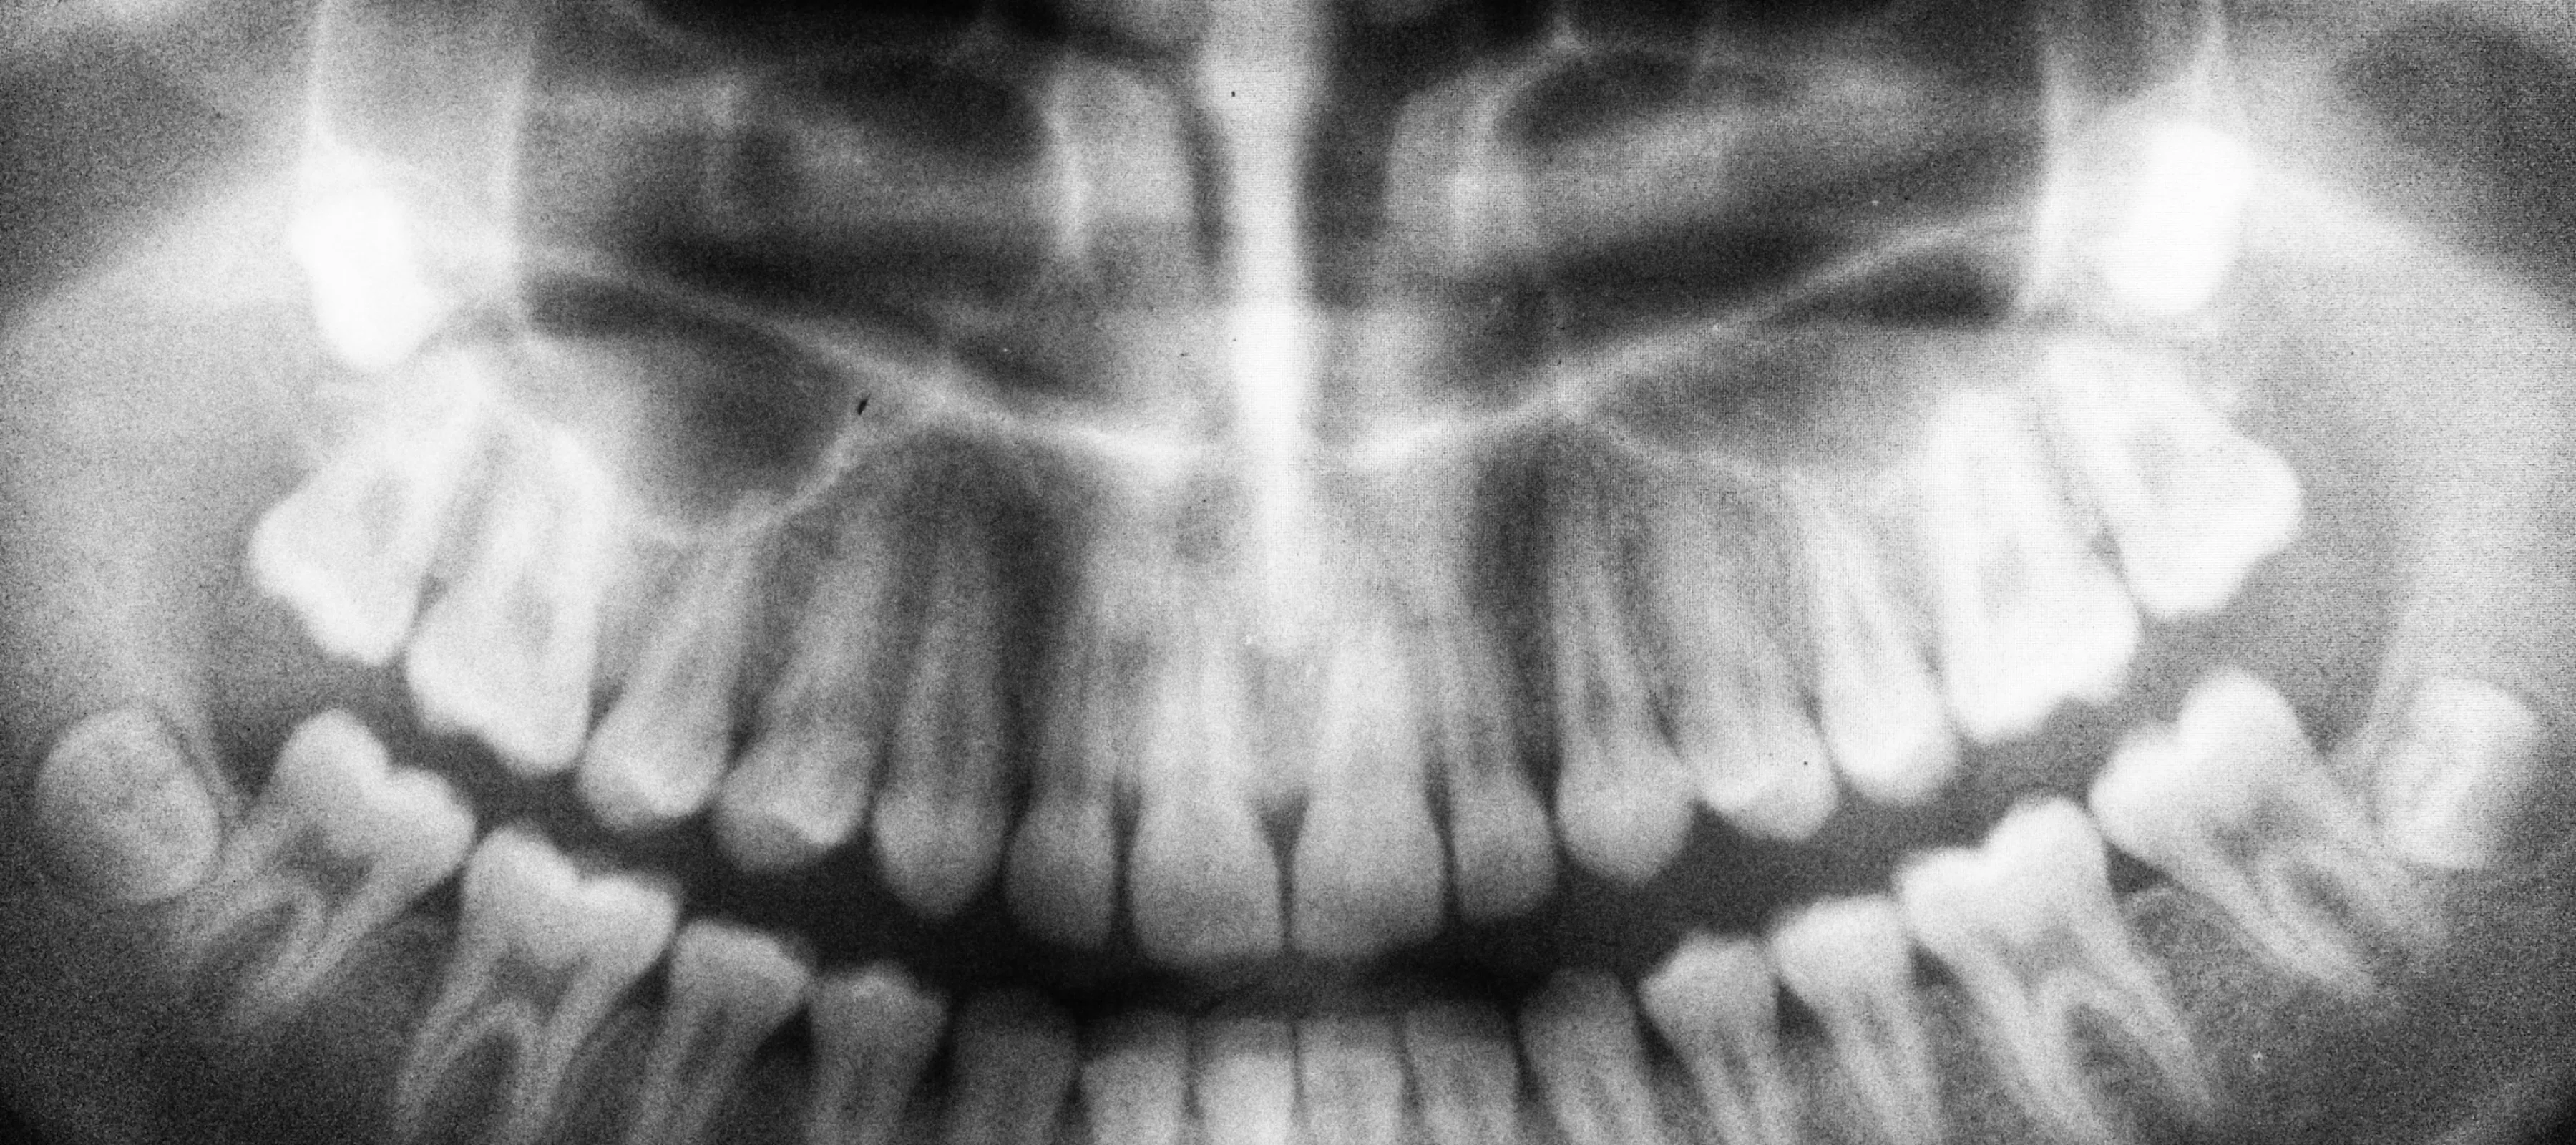

Black and white panoramic dental X-ray showing full adult teeth and jaw structure

Digital X-Rays

We use low-radiation imaging that delivers crystal-clear pictures in seconds. We can spot what needs attention and walk you through it together. You don't have to deal with the old-school wait or mess of film.